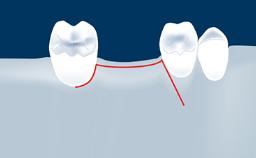

In this short microlearning module on digitally guided sinus floor elevation, we delve into a specialized aspect of the digital workflow for implant-guided surgery, focusing on the use of digital guides in the sinus floor elevation technique.

- define the manufacturing process of digital guides for SFE